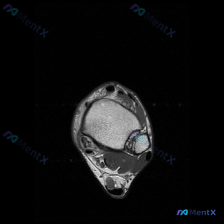

看到一个挺有代表性的读片问题,整理一下完整的分析思路分享给大家。 病例基础信息 这是一份单张踝关节MRI T2序列轴位图像,临床疑问是观察到「软组织积液」,需要解读。 影像结构完整评估 我们先把影像上能看到的结构逐一梳理清楚: 1. 骨骼结构:可见胫腓骨远端截面,骨皮质轮廓清晰,骨髓信号没有异常高信...